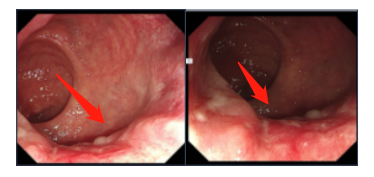

术后2个月,小区一解封安**马上来医院复查,傅教授肛门指诊并结合电子结肠镜检查:见齿状线上约1cm吻合口粘膜光滑完整、无狭窄,可以还纳。安**又惊又喜,不是还没有到3个月吗?我可以还纳了?

吻合口恢复良好

直肠癌术后什么时候可以还纳?安**直肠癌尚属早期、病理回报切缘干净、无周围淋巴结转移,排便良好,吻合口通畅无狭窄,择期可行造口还纳术。如能较快还纳,肠道功能、连续性和排便习惯的恢复也会更快。